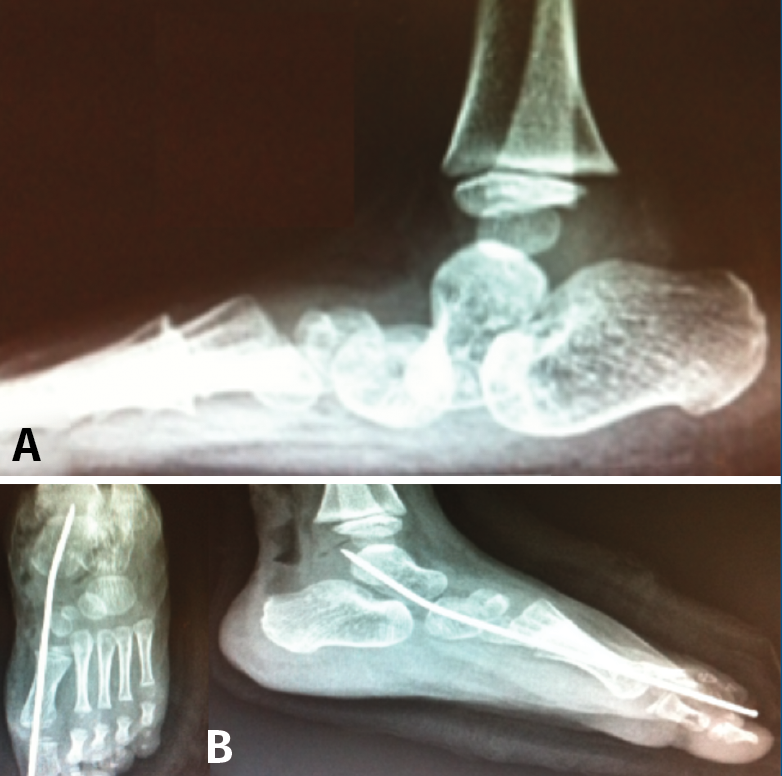

El manejo es casi siempre quirúrgico y se basa en una liberación periastragalina extensa, corrección del equino del retropié, liberación de las fuerzas pronadoras y trasplante del TA sobre la cabeza del astrágalo. Dobbs(19) describió un tratamiento miniinvasivo basado en yesos seriados “antiponseti” reduciendo progresivamente la articulación TN llevando el pie en equino y aducción. Finalmente, se procede a una fijación temporal de la alineación TN con AK y corrección del equino mediante tenotomía de Aquiles (Figura 17). En caso de reducción insuficiente, se añade una liberación TN para permitir la reducción completa, que se mantiene temporalmente mediante AK retrógrada.

Figura 17. Astrágalo vertical congénito. A: diagnóstico radiológico; B: técnica Dobbs percutánea.